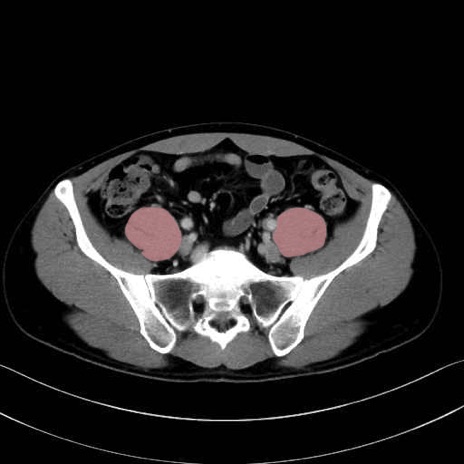

2. 腸腰筋群と骨盤底筋

大腰筋 (Psoas major)

腸骨筋 (Iliacus)